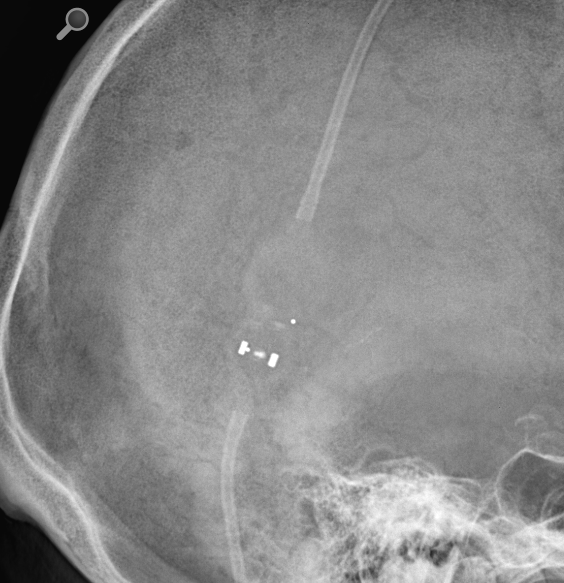

Certas Shunt Valve X Ray . Codman certas plus medical equipment pdf manual download. certas™ plus programmable valve offers the ability to optimize the opening pressure of a shunt system before and after. view and download integra codman certas plus manual online. the purpose of this study was to provide a single reference containing radiographic depictions of the major programmable shunt valves in current use as well as information for accurate reporting of shunt valve settings. indications the codman® certas™ plus programmable valve is an implantable device that provides constant.

the purpose of this study was to provide a single reference containing radiographic depictions of the major programmable shunt valves in current use as well as information for accurate reporting of shunt valve settings. indications the codman® certas™ plus programmable valve is an implantable device that provides constant. Codman certas plus medical equipment pdf manual download. view and download integra codman certas plus manual online. certas™ plus programmable valve offers the ability to optimize the opening pressure of a shunt system before and after.